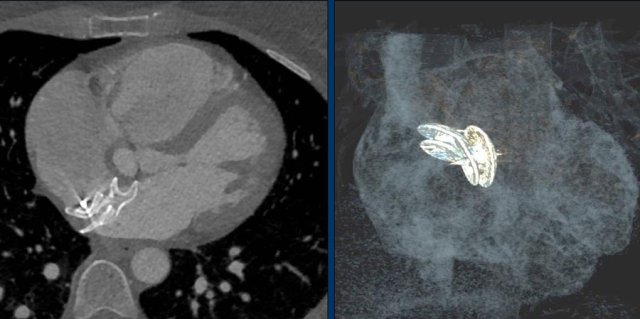

Images of a patient with an ASD and an Amplatz closure device.

Here a patient with a larger defect, that was closed with two devices.

Continue with the CT-images.

Transverse CT-image and coronal reconstruction of the same patient.

This patient has three closure devices.

Dislocation of the closure device.

CT demonstrates, that the Amplatz device is dislocated into the aortic arch.